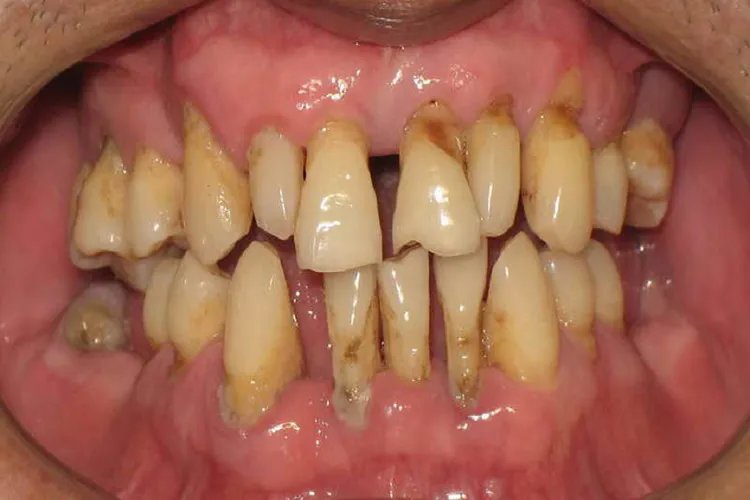

牙周炎图片

的有关信息介绍如下:概述牙周炎多表现为牙龈红肿,刷牙时易出血,严重时形成牙周袋,甚至牙齿出现松动移位。牙周炎可能与牙菌斑、牙石、食物嵌塞、解剖因素、口腔不良习惯等原因有关。症状牙周炎分类尚不成熟,主要包括慢性牙周炎、侵袭性牙周炎和伴有全身疾病的牙周炎。各种牙周炎的临床表现相似,常见症状有牙龈红肿、刷牙时易出血、牙龈退缩、口腔异味、咬合不适或疼痛、牙松动等。牙周炎严重时可导致牙周组织破坏,形成牙周袋,造成附着丧失和牙槽骨吸收。晚期当牙周组织破坏到一定程度,牙发生松动移位甚至脱落。其间可因牙周膜炎症出现咬合无力、不适或疼痛。常出现一系列伴发病变,如牙龈退缩、牙根暴露、根分叉病变、食物嵌塞、牙根面敏感、根面龋、牙周脓肿、逆行性牙髓炎等。